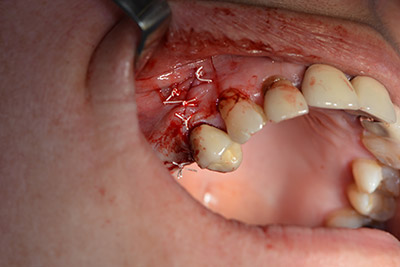

Класическият разрез (крестално, букално освобождаване) и подготовката на мукопериостално ламбо осигуряват добра видимост.

Използвана е абсорбираща мембрана като бариера на букалната страна и покритие на аугментацията. Накрая са поставени устойчиви на слюнка конци (Фиг. 15 до 19).